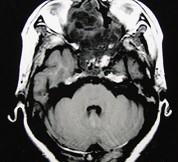

问题 女性,41岁,鼻腔流脓涕3年,鼻部面部肿胀1年,近来加重,MRI检查如图,请选择最可能诊断()

选项 A.鼻腔内囊肿 B.鼻腔内出血 C.鼻腔软骨瘤 D.鼻咽癌 E.鼻腔血管瘤

答案 C